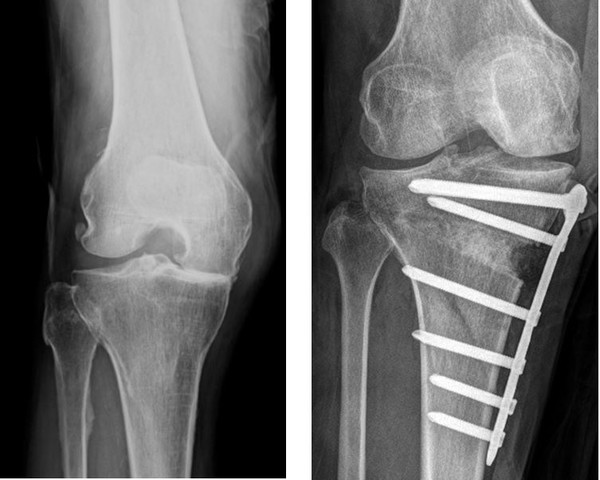

퇴행성 관절염

골관절염은 무릎 관절염의 가장 일반적인 형태로 관절연골이 점차 마모돼 천천히 진행되는 퇴행성 질환이다. 대부분 중년 및 노년층에서 흔히 나타난다. 증상은 점진적으로 발생하는데 강직되고 부기가 생겨 무릎관절을 접는 데 많은 어려움이 생긴다. 퇴행성 관절염은 통증이 활동 후 증가해서 잠잘 때 아픈 특징이 있다. 걷거나 뛸 때 심해지며, 안정시 완화되는 양상을 보인다.

퇴행성관절염은 관절연골의 퇴행성 변화에 의해 발생하므로 한번 손상된 관절은 완전히 회복시킬 수는 없다. 따라서 평소 건강한 식습관과 꾸준한 운동으로 체중을 관리해 발병위험을 낮추고 정기검진을 받아 예방하는 것이 최선이다. 그리고 무릎 통증이 느껴지면 방치하지 말고 전문의의 상담을 받아 악화되지 않도록 조기에 대응하는 것이 바람직하다.